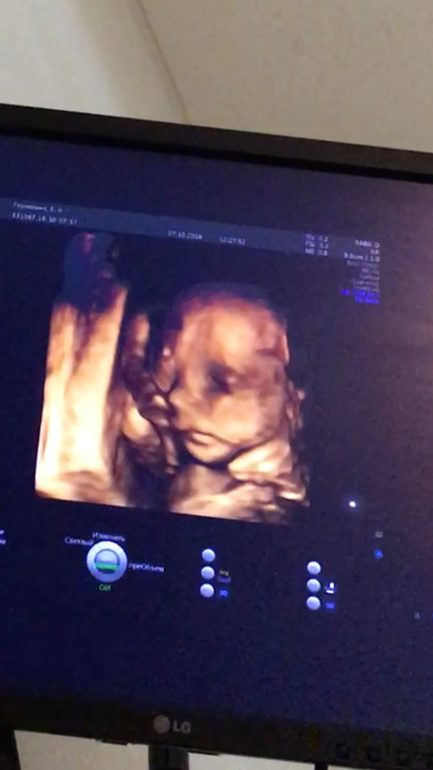

Более менее не инопланетянин после 20 недели. У нас было так, что врач сначала делает само УЗИ стандартное, всё измеряет все объясняет и показывает, а в конце в качестве развлечения уже переключает на аппарате на 3D и мы смотрим, делает снимки если ракурсы хорошие

Я думаю тут индивидуально - зависит от врача и от клиники. У нас всё УЗИ наверное минут 20-30 заняло, а 3D в конце ну минут 5 наверное. Смотря ещё как лежит..с сыном мы никак не могли лица поймать на 3D а на остальное и смотреть не интересно)) он утыкался лицом в стенку матки и всё тут..доча более сговорчива, видимо как все девочки любит фотать😁